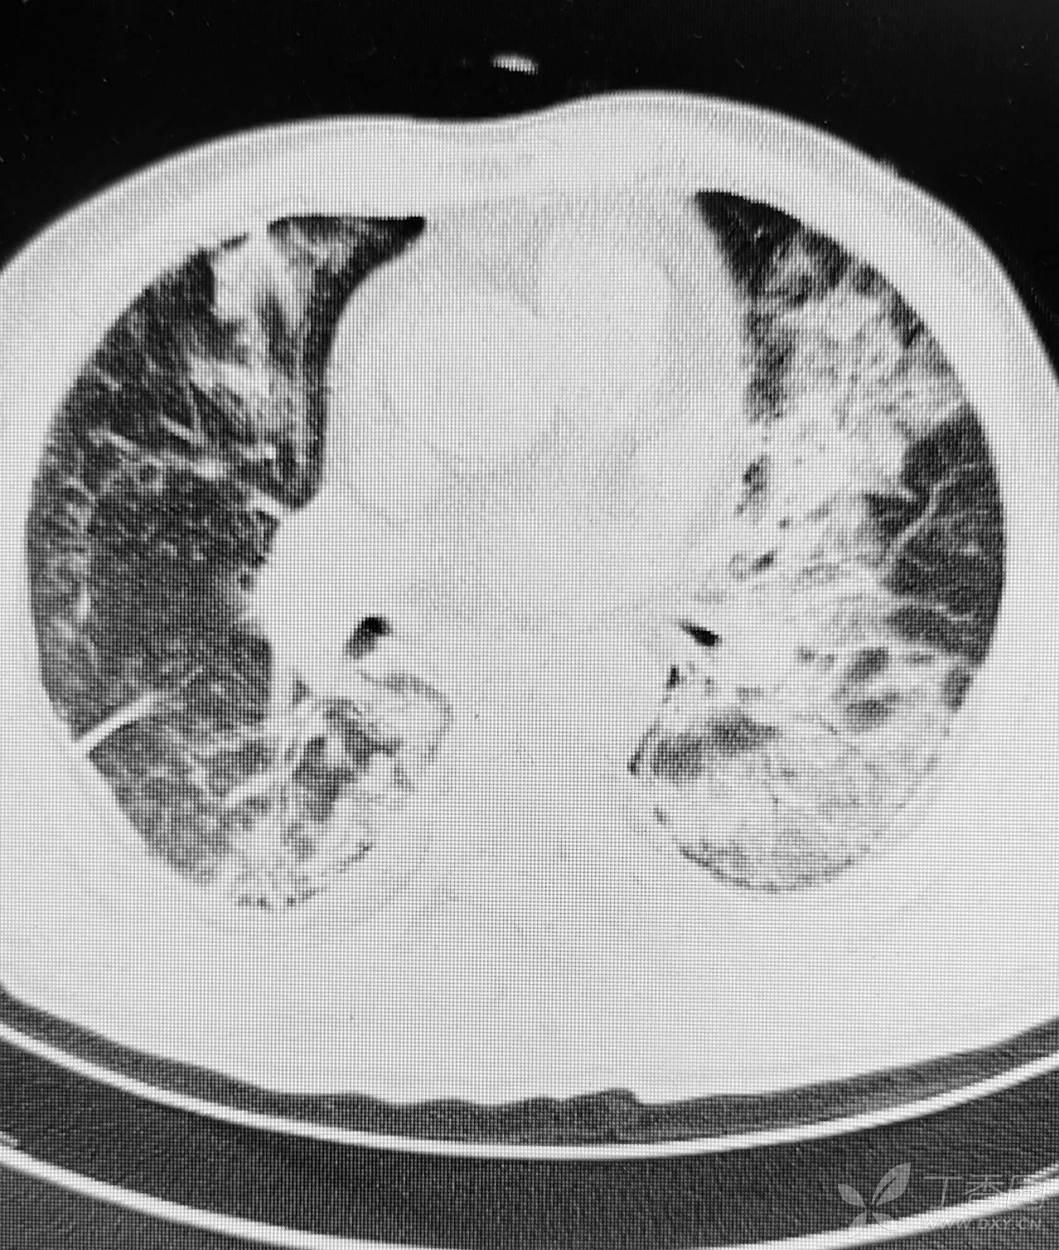

直肠癌术后两个月,接受放化疗一个月。白细胞危急值。

停化疗放疗,升白药物。白细胞增高了。

血小板仍低,血红蛋白开始降低。

胸部影像如图。

目前有血培养阳性,病原菌难以命中。痰培养阳性。